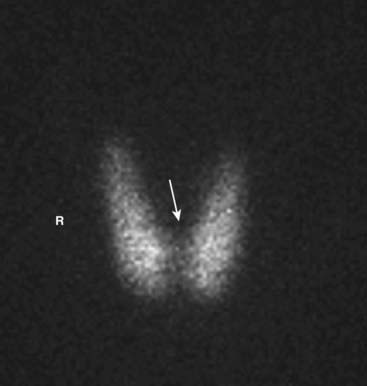

image Unlike the convention used for viewing other studies in radiology, the patient’s right side is not always on your left in nuclear scans. This can be confusing, so make sure you look for the labels on the scan (Fig. 1).

image

Figure 1 Normal bone scan.

Anterior and posterior views are frequently obtained, since each view brings different structures closer to the gamma camera for optimum imaging, e.g., the sternum on the anterior view (solid white arrow) and the spine on the posterior view (dotted white arrow). Notice that the kidneys are normally visible on the posterior view (white oval). Unlike the convention used in viewing other studies in radiology, the patient’s right side is not always on your left. On posterior views, the patient’s right side is on your right. This can be confusing, so make sure you look for the labels on the scan. In many cases a white marker dot will be located on the patient’s right side (white circles).